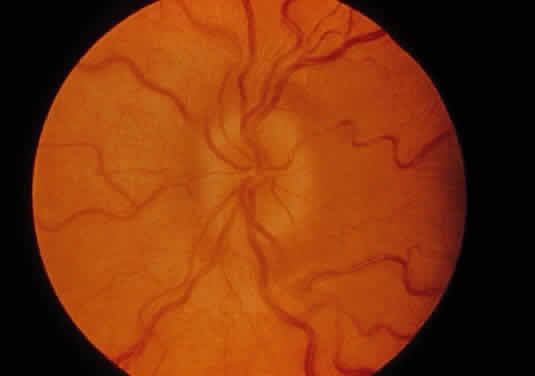

Corneal clouding (Fig. 10), hyperopic astigmatism, and a mild retinopathy with surface-wrinkling maculopathy (Fig. 11) appear to be the constant ocular triad.75 Some patients have retinal vascular tortuosity, optic nerve head swelling (Fig. 12), visual field defects, and abnormalities in color vision. Visual complaints are uncommon.

Fig. 10. Mild corneal clouding in a child with mucolipidosis III. (Traboulsi E, Maumenee I: Ophthalmologic findings in mucolipidosis III. Am J Ophthalmol 102:529, 1986)

Fig. 11. Surface-wrinkling maculopathy in a patient with mucolipidosis III. (Traboulsi E, Maumenee I: Ophthalmologic findings in mucolipidosis III. Am J Ophthalmol 102:529, 1986)

Fig. 12. Optic nerve head swelling in a patient with mucolipidosis III. (Traboulsi E, Maumenee I: Ophthalmologic findings in mucolipidosis III. Am J Ophthalmol 102:529, 1986)